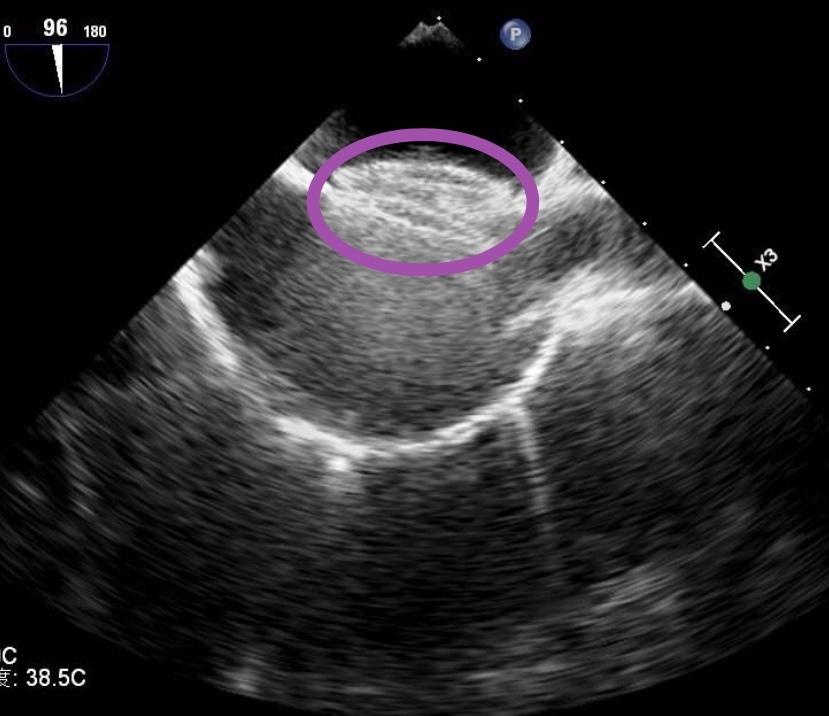

诊断依靠经胸/经食管超声心动图(白色箭头所指处),超声声学造影可发现潜在的卵圆孔未闭(黄色箭头所指处)。